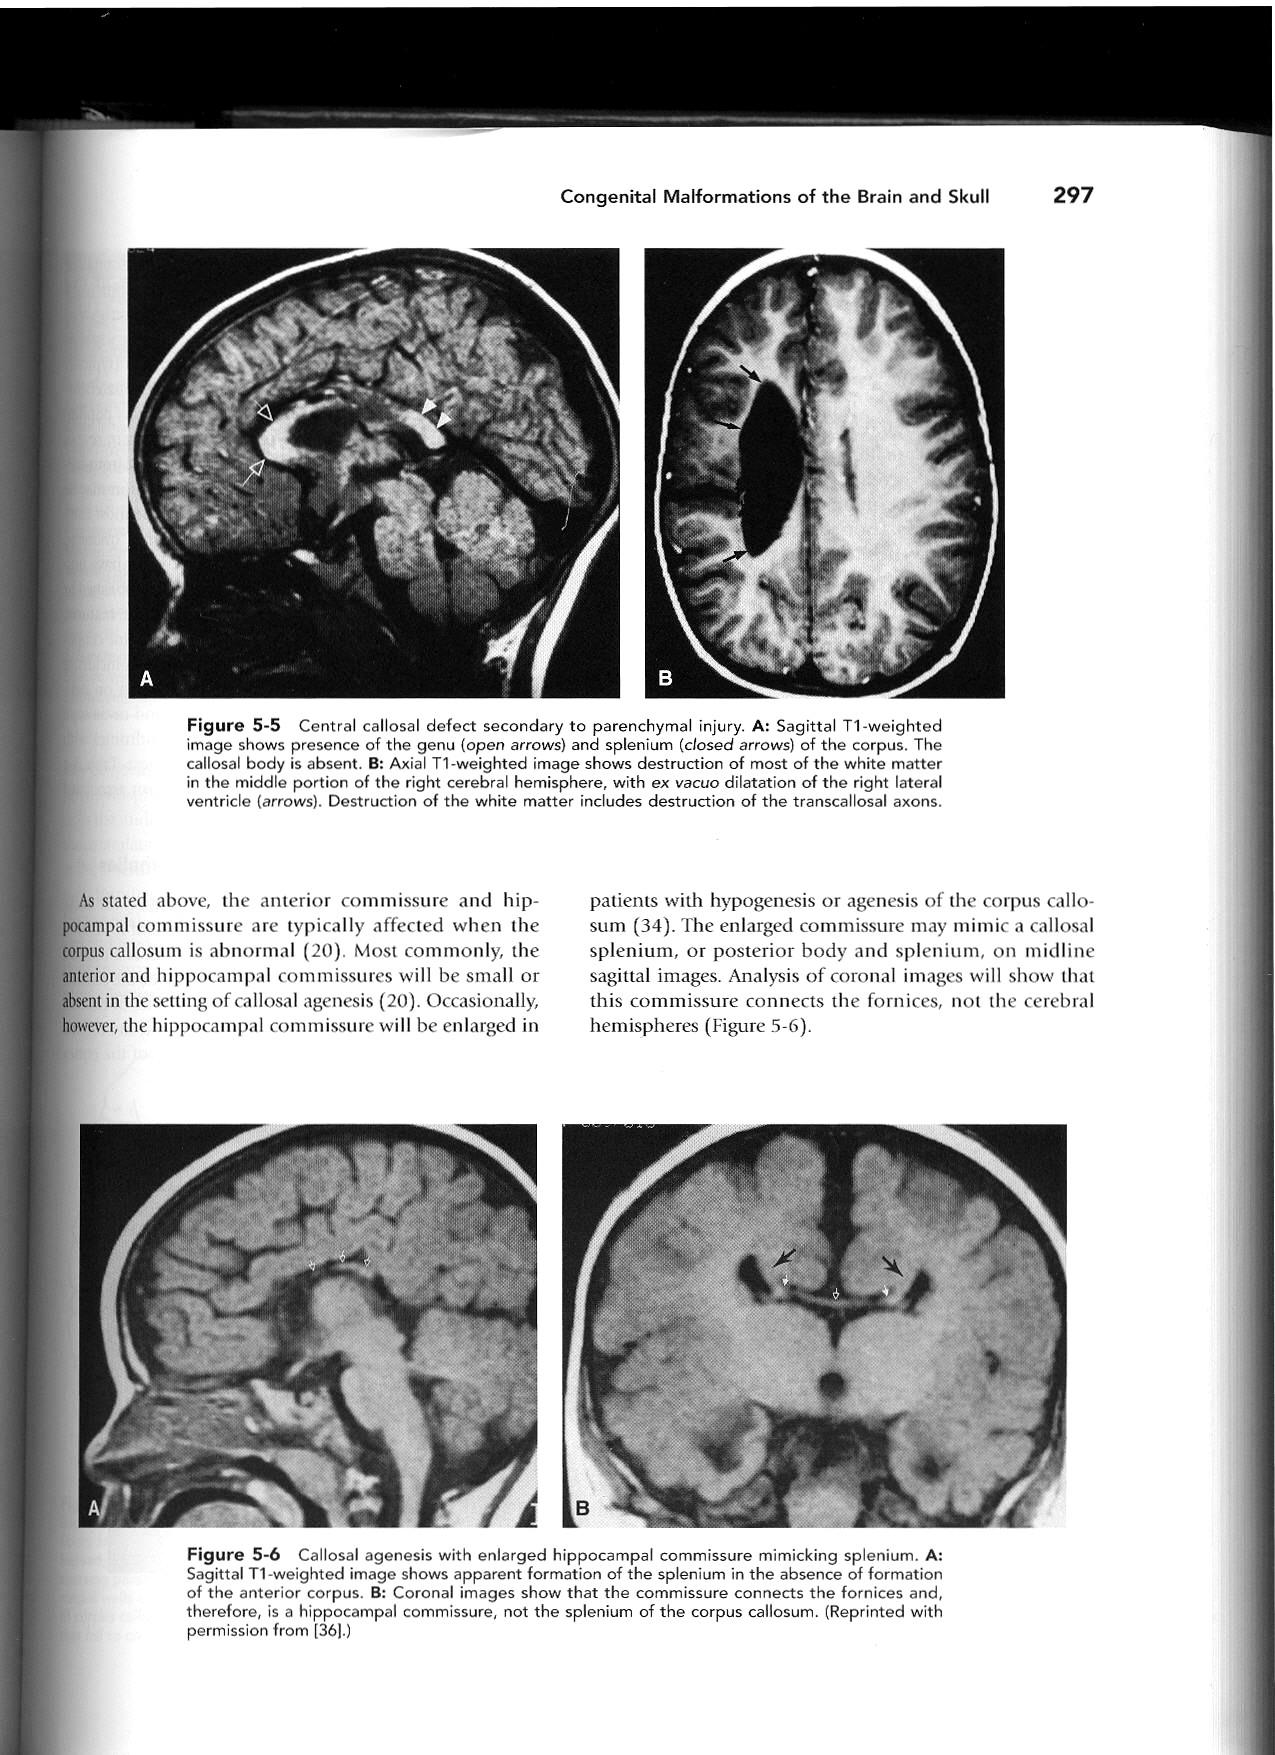

Cingulate gyrus (black arrows) “mirrors” the development of the corpus callosum.

Enlarged HC connects fornices, not cerebral hemispheres